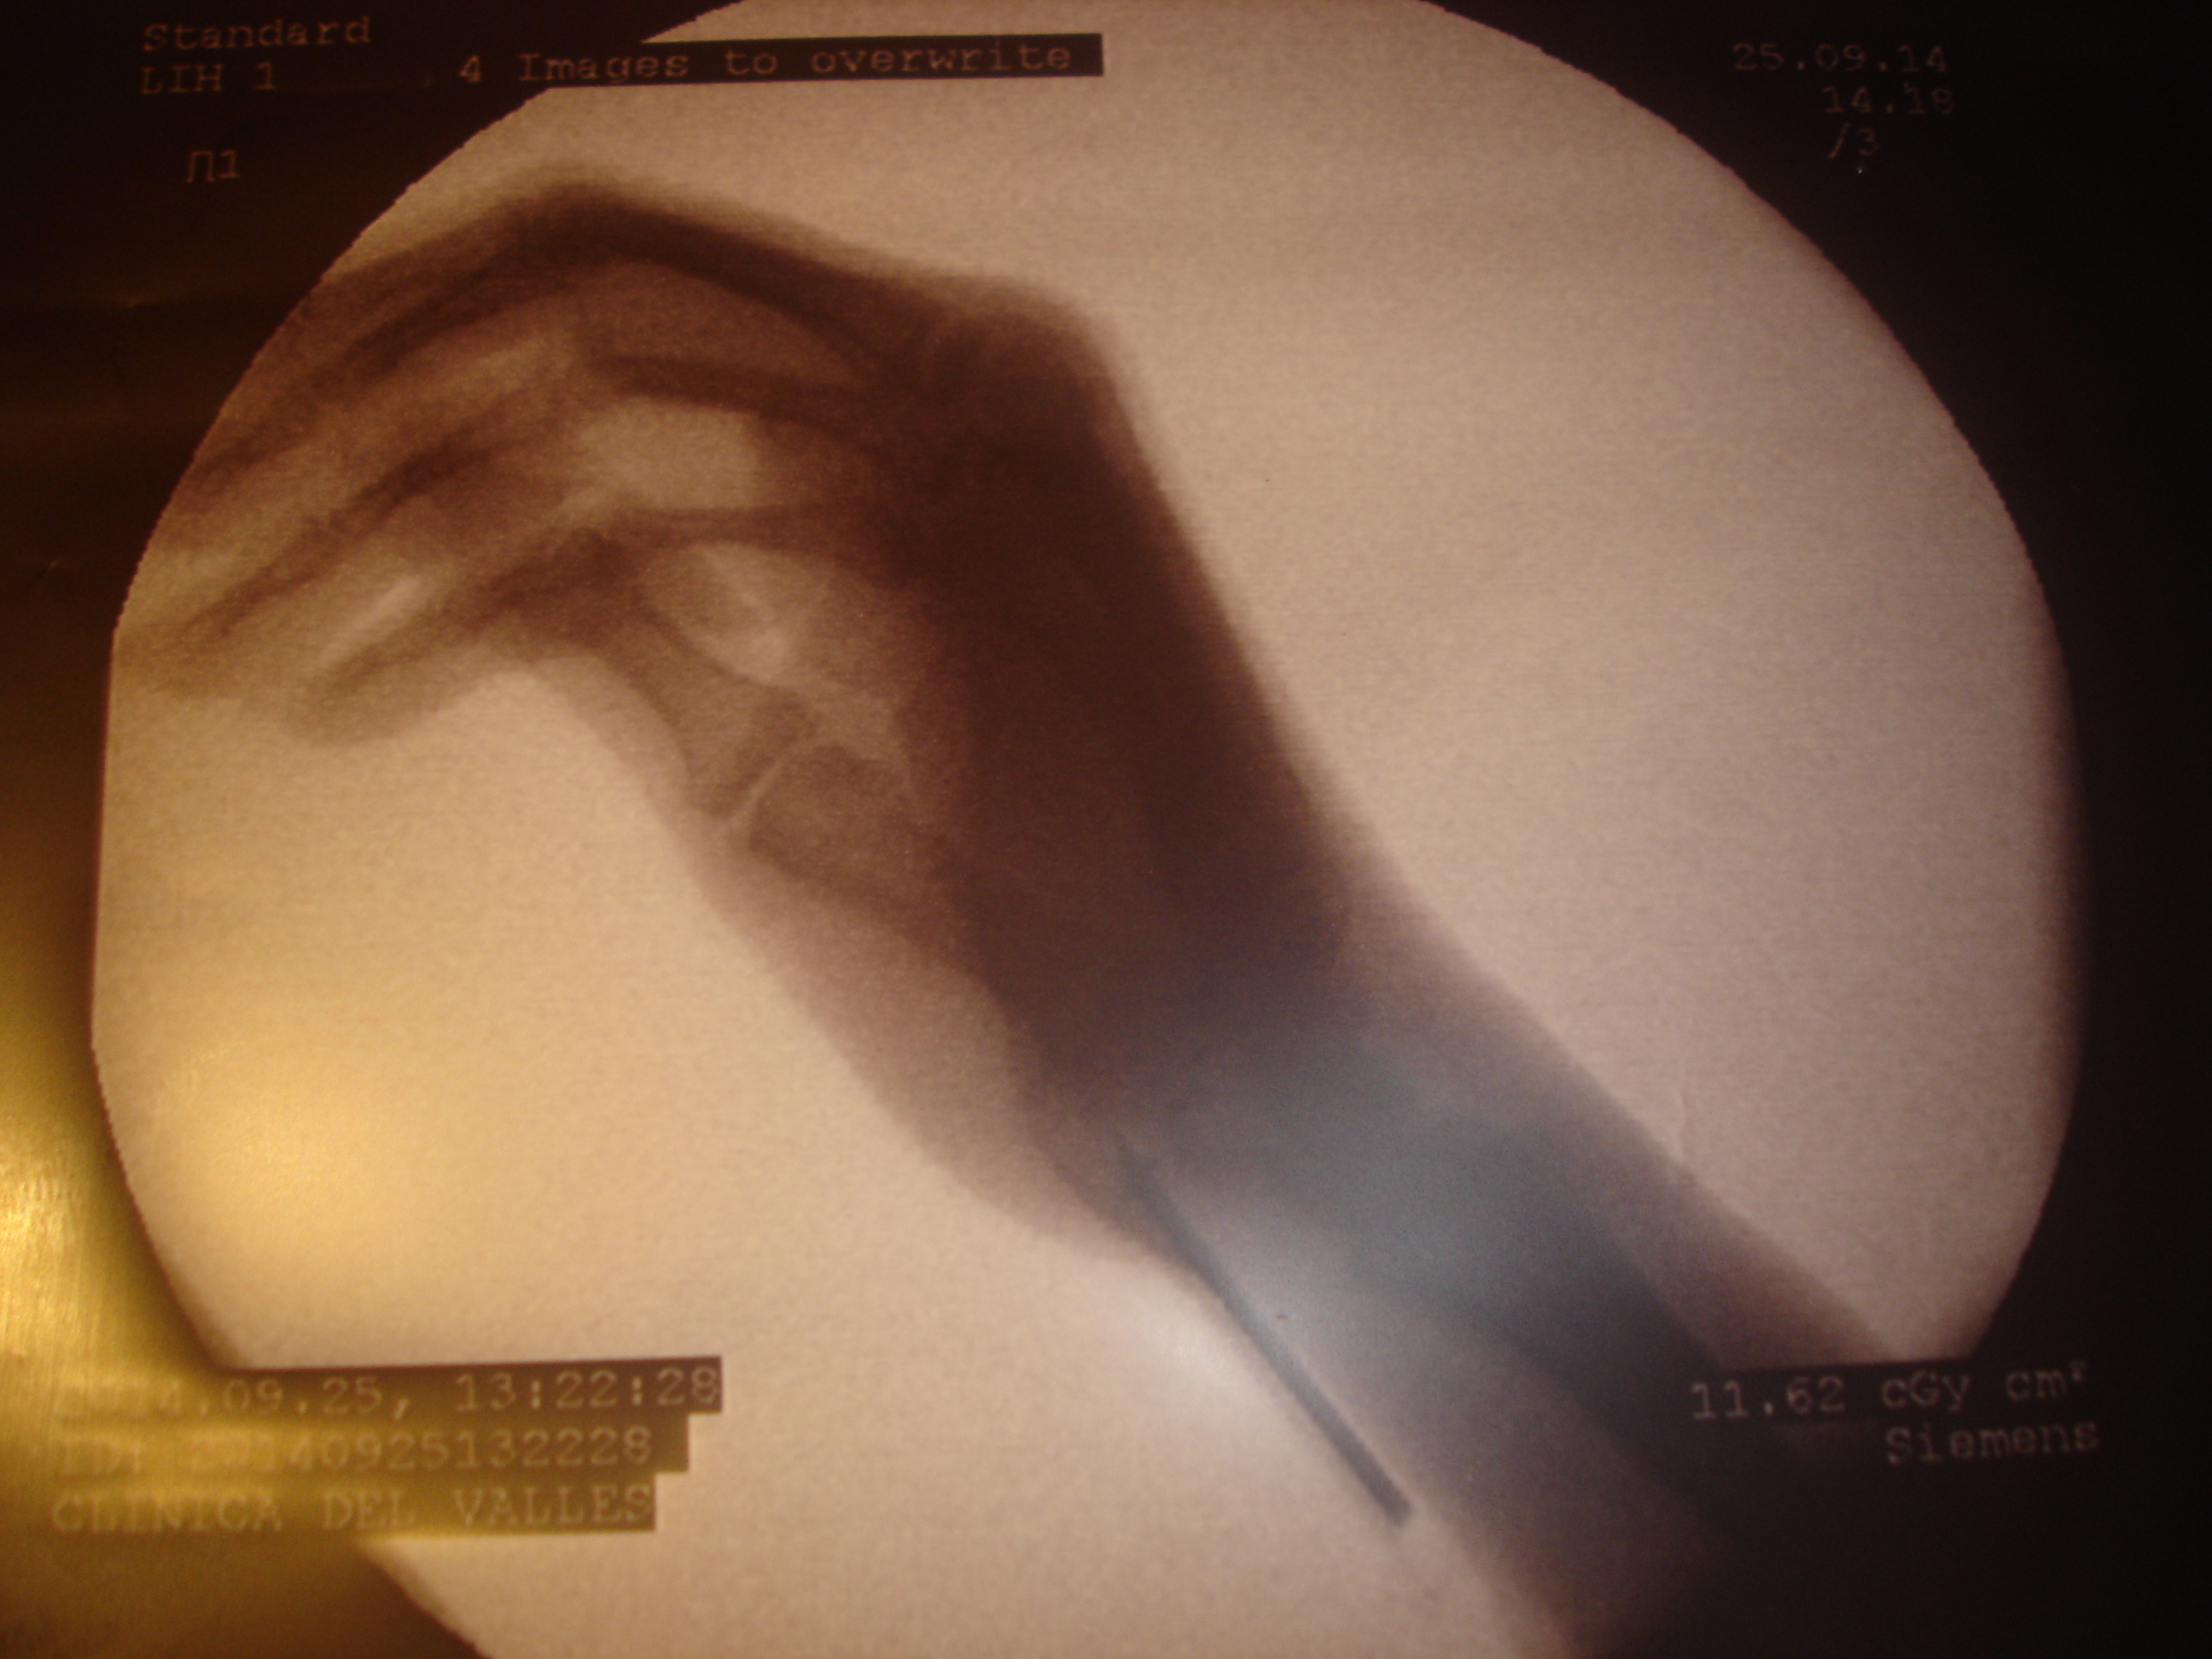

aspecto antes de la RX con las calcificaciones

Uno de los procesos que mejor evolucionan tras la colocación de implantes de oro periarticulares es la rizartrosis del pulgar. Puede que al no ser una articulación de carga la respuesta al tratamiento sea más rápida. La degeneración articular con la pérdida de la congruencia anatómica no es un obstáculo para la recuperación funcional; la mejoría de la movilidad y la fuerza de prensión digital son notables en los casos tratados, así como la disminución-supresión del dolor. Parece cada día más evidente el relevante papel de los tejidos blandos articulares y periarticulares en la morbilidad  articular. Uno de los efectos biomédicos descritos en experimentación animal es la competencia local del oro con el calcio que se observa en las exóstosis y calcificaciones periarticulares. Se aprecia en las siguientes RX el caso de una paciente con rizartrosis de pulgar bilateral que requería una ingesta diaria de diclofenaco durante 12 años, que suspendió al día siguiente de la intervención hace unos 4 meses. Puede verse un cambio significativo en la calcificación de la mano izquierda. Es uno de los casos (bilateral) en el que el resultado funcional (movilidad y fuerza).